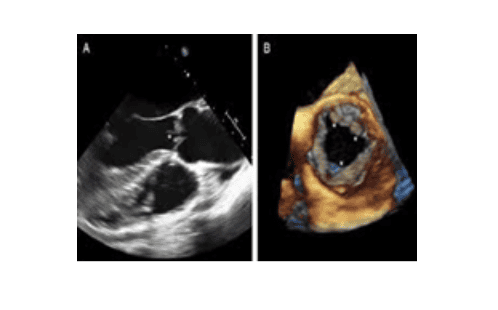

Siêu âm không sử dụng các bức xạ ion hóa như chụp X-quang hay chụp cắt lớp vi tính. Hình ảnh thu được từ siêu âm là hình ảnh thời gian thực nên có thể cho thấy cấu trúc và chuyển động của các cơ quan trong cơ thể như tim hay chuyển động của máu trong lòng mạch.

Hiện nay siêu âm đã phát triển và hình thành nhiều kỹ thuật mới hiện đại như siêu âm màu, siêu âm 3D định dạng dữ liệu sóng âm để hiển thị hình ảnh 3D hay siêu âm 4D ngoài định dạng hình ảnh 3D còn có thể mô tả những cơ quan, nội tạng hay thai nhi dưới dạng các video sinh động và chân thực nhất.

Hình ảnh siêu âm Doppler có thể giúp các bác sỹ quan sát và đánh giá:

- Sự tắc nghẽn lưu lượng máu do xuất hiện cục máu đông

- Khối u hoặc các dị tật mạch máu bẩm sinh

- Đánh giá lưu lượng máu cung cấp đến các cơ quan khác nhau như tinh hoàn đối với nam hoặc buồng trứng đối với nữ. Tăng lưu lượng máu bất thường có thể là dấu hiệu của nhiễm trùng